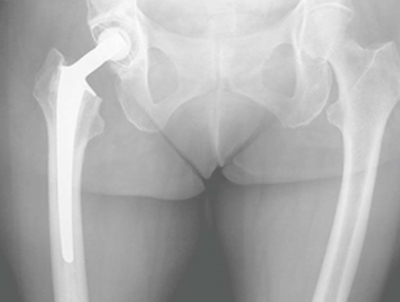

Bei Patienten mit stark verminderter Knochenqualität (Osteoporose) ist nach wie vor die Fixierung der Prothese mit sogenanntem Knochenzement das Verfahren der Wahl. Das Bein kann unmittelbar nach der OP vollbelastet werden. Dadurch ist häufig eine schnelle Mobilisation und Reintegration in den Alltag gewährleistet. Sekudäre Erkrankungen bei verminderter Mobilität (Thrombosen/ Embolien ect.) sollen dadurch vermieden werden.

Die SP II Schaftprothese kann bei ausgeprägter Osteoporose mit einer Polyethylenpfanne gekoppelt werden (beidseitig zementiert), bei guter knöcherner Substanz pfannenseitig kann eine zementfreie Pfanne implantiert werden (Hybridprothese).